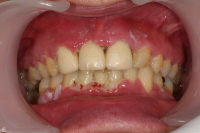

Ödematös, rodnad och blödande gingiva.

Förekomst av gingivala hyperplasier med djupa tandköttsfickor och svåra hygienförhållanden som följd.

Karakteriseras av approximala nekrotiska och fibrintäckta sår (nedsmälta papiller) som är smärtsamma vid beröring och mycket lättblödande.

Svullnad, rodnad och ömhet, ibland värk.